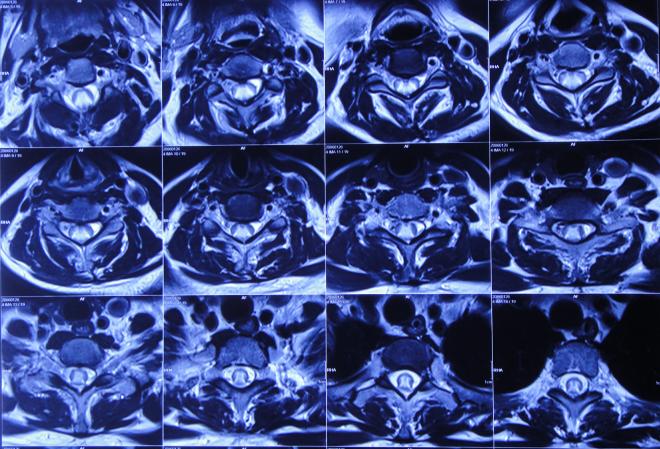

入院治疗3天即2019年6月24日,进行了脑室腹壁外引流术,术后当天查头颅CT示脑室引流状态( 图-18 )。

图-18: 2019年6月24日头颅CT

入院治疗6天即2019年6月27日,查头颅CT示脑室缩小( 图-19 ),但有少量出血,当天给予脑室引流管调整术。

图-19: 2019年6月27日头颅CT

术后次日复查头颅CT示引流管位置良好( 图-20 )。

图-20: 2019年6月28日头颅CT

入院治疗10天即2019年7月1日,复查头颅CT示脑室缩小、出血基本消失( 图-21 )。

图-21: 2019年7月1日头颅CT